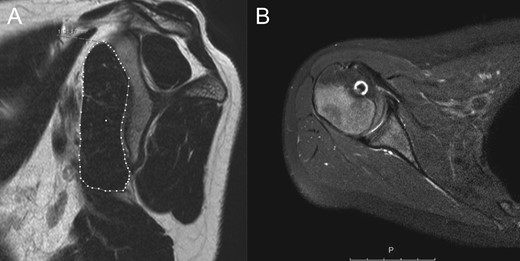

MRI 1-year after surgery. In the sagittal view there are no sign of atrophy or fatty infiltration of the subscapularis muscle (A). The subscapularis tendon is healed in an anatomical position (B).